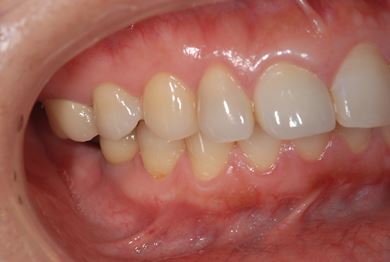

インプラントの症例写真 IMPLANT

インプラント治療+セラミック治療

| 主訴 | 前歯や、下の奥など、何本か気になる歯がある。 | ||||||||||||||||||||||||||||||||

| 治療方針 | インプラント治療により、機能的・審美的回復を行う。 | ||||||||||||||||||||||||||||||||

| 治療内容 | インプラント2本、メタルボンドセラミッククラウン4本、ジルコニアフレームオールセラミッククラウン1本(オールセラミック用土台1本) | ||||||||||||||||||||||||||||||||